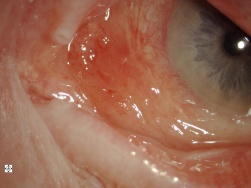

Conjunctival amyloidosis usually appears as confluent fusiform lesions or polypoidal papules that have a salmon-colored or yellow-pink color. Any conjunctival surface may be involved, but the superior fornix and tarsal conjunctiva are the most frequently affected. This deposition may result in ptosis. Patients may also present with recurrent subconjunctival hemorrhage from the accumulation of amyloid in the walls of the blood vessels. The eyelid, extraocular muscles, and lacrimal gland may also be affected by amyloidosis.

Figure 1a & 1b: Slit lamp photo of the conjunctival amyloidosis